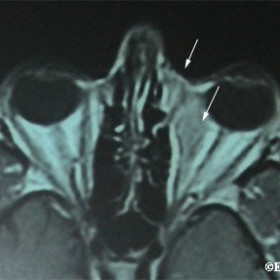

Nasal orbital lymphoma with subcutaneous extension

Magnetic resonance imaging (T2), demonstrates an nasal orbital lymphoma with subcutaneous extension (arrows).